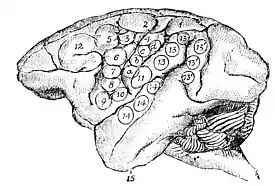

Hitzig's investigations, published in Berlin in 1874, give all the results gained up to that time by the stimulation experiments. Ferrier's book, "The Functions of the Brain," London, 1876, better known  Fig. 2.—Lateral Aspect of Monkey's Brain, showing the relative positions of the so-called "Motor Centers" in the left Cerebral Hemisphere. Ferrier. to English readers, has special merit in two respects. It displays a very intelligent comprehension of the consequences of electrical stimulation, and seems to give a juster account of the motor regions in the monkey's brain than was furnished by Hitzig.

Fig. 2.—Lateral Aspect of Monkey's Brain, showing the relative positions of the so-called "Motor Centers" in the left Cerebral Hemisphere. Ferrier. to English readers, has special merit in two respects. It displays a very intelligent comprehension of the consequences of electrical stimulation, and seems to give a juster account of the motor regions in the monkey's brain than was furnished by Hitzig.

Figs. 2 and 3 will show the character and results of these experiments in sufficient detail.

When center No. 1 is stimulated, the hind-limb on the opposite side of the body advances as in the act of walking; when No. 5 is stimulated, the opposite arm and hand reach forward as if to touch something. These movements go together and are essentially the  Fig. 3.—Upper Aspect of Monkey's Brain, showing the relative positions of some of the so-called "Motor Centers" in the left Cerebral Hemisphere, (Ferrier.) same. Centers 2 and 3 work together; when 2 is stimulated, there are combined movements of the opposite thigh, leg, and foot, and the foot is brought to the middle line of the body as in scratching that part, or in seizing something with the foot; 3 gives movements of the tail. An interesting fact should be noted at this point. There is no center No. 2 in the brain of cat, dog, or jackal, while No. 3 is present in each. These animals do not grasp with the foot, and the monkey alone uses the rear foot for seizing. That No. 2 should be present, and of great size, in the monkey's brain, while absent elsewhere, is confirmatory of the accuracy of the experiments. The centers marked a, b, c, d, are on the ascending parietal convolution. When stimulus is applied there, the fingers and wrist move with separate and combined movements

Fig. 3.—Upper Aspect of Monkey's Brain, showing the relative positions of some of the so-called "Motor Centers" in the left Cerebral Hemisphere, (Ferrier.) same. Centers 2 and 3 work together; when 2 is stimulated, there are combined movements of the opposite thigh, leg, and foot, and the foot is brought to the middle line of the body as in scratching that part, or in seizing something with the foot; 3 gives movements of the tail. An interesting fact should be noted at this point. There is no center No. 2 in the brain of cat, dog, or jackal, while No. 3 is present in each. These animals do not grasp with the foot, and the monkey alone uses the rear foot for seizing. That No. 2 should be present, and of great size, in the monkey's brain, while absent elsewhere, is confirmatory of the accuracy of the experiments. The centers marked a, b, c, d, are on the ascending parietal convolution. When stimulus is applied there, the fingers and wrist move with separate and combined movements